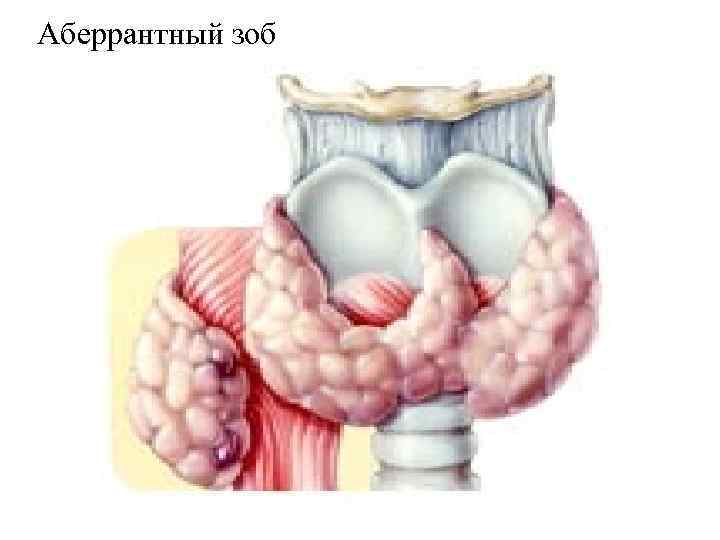

Аберрантный зоб

Аберрантный зоб